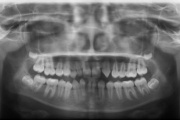

Ühepoolse lõhega lapse hambumus (puudub hammas lõhe piirkonnas).

Kaasasündinud hammaste puudumine

Sagedamini puuduvad hambad: teised premolaarid, ülemised lateraalsed intsisiivid, alumised tsentraalsed intsisiivid.